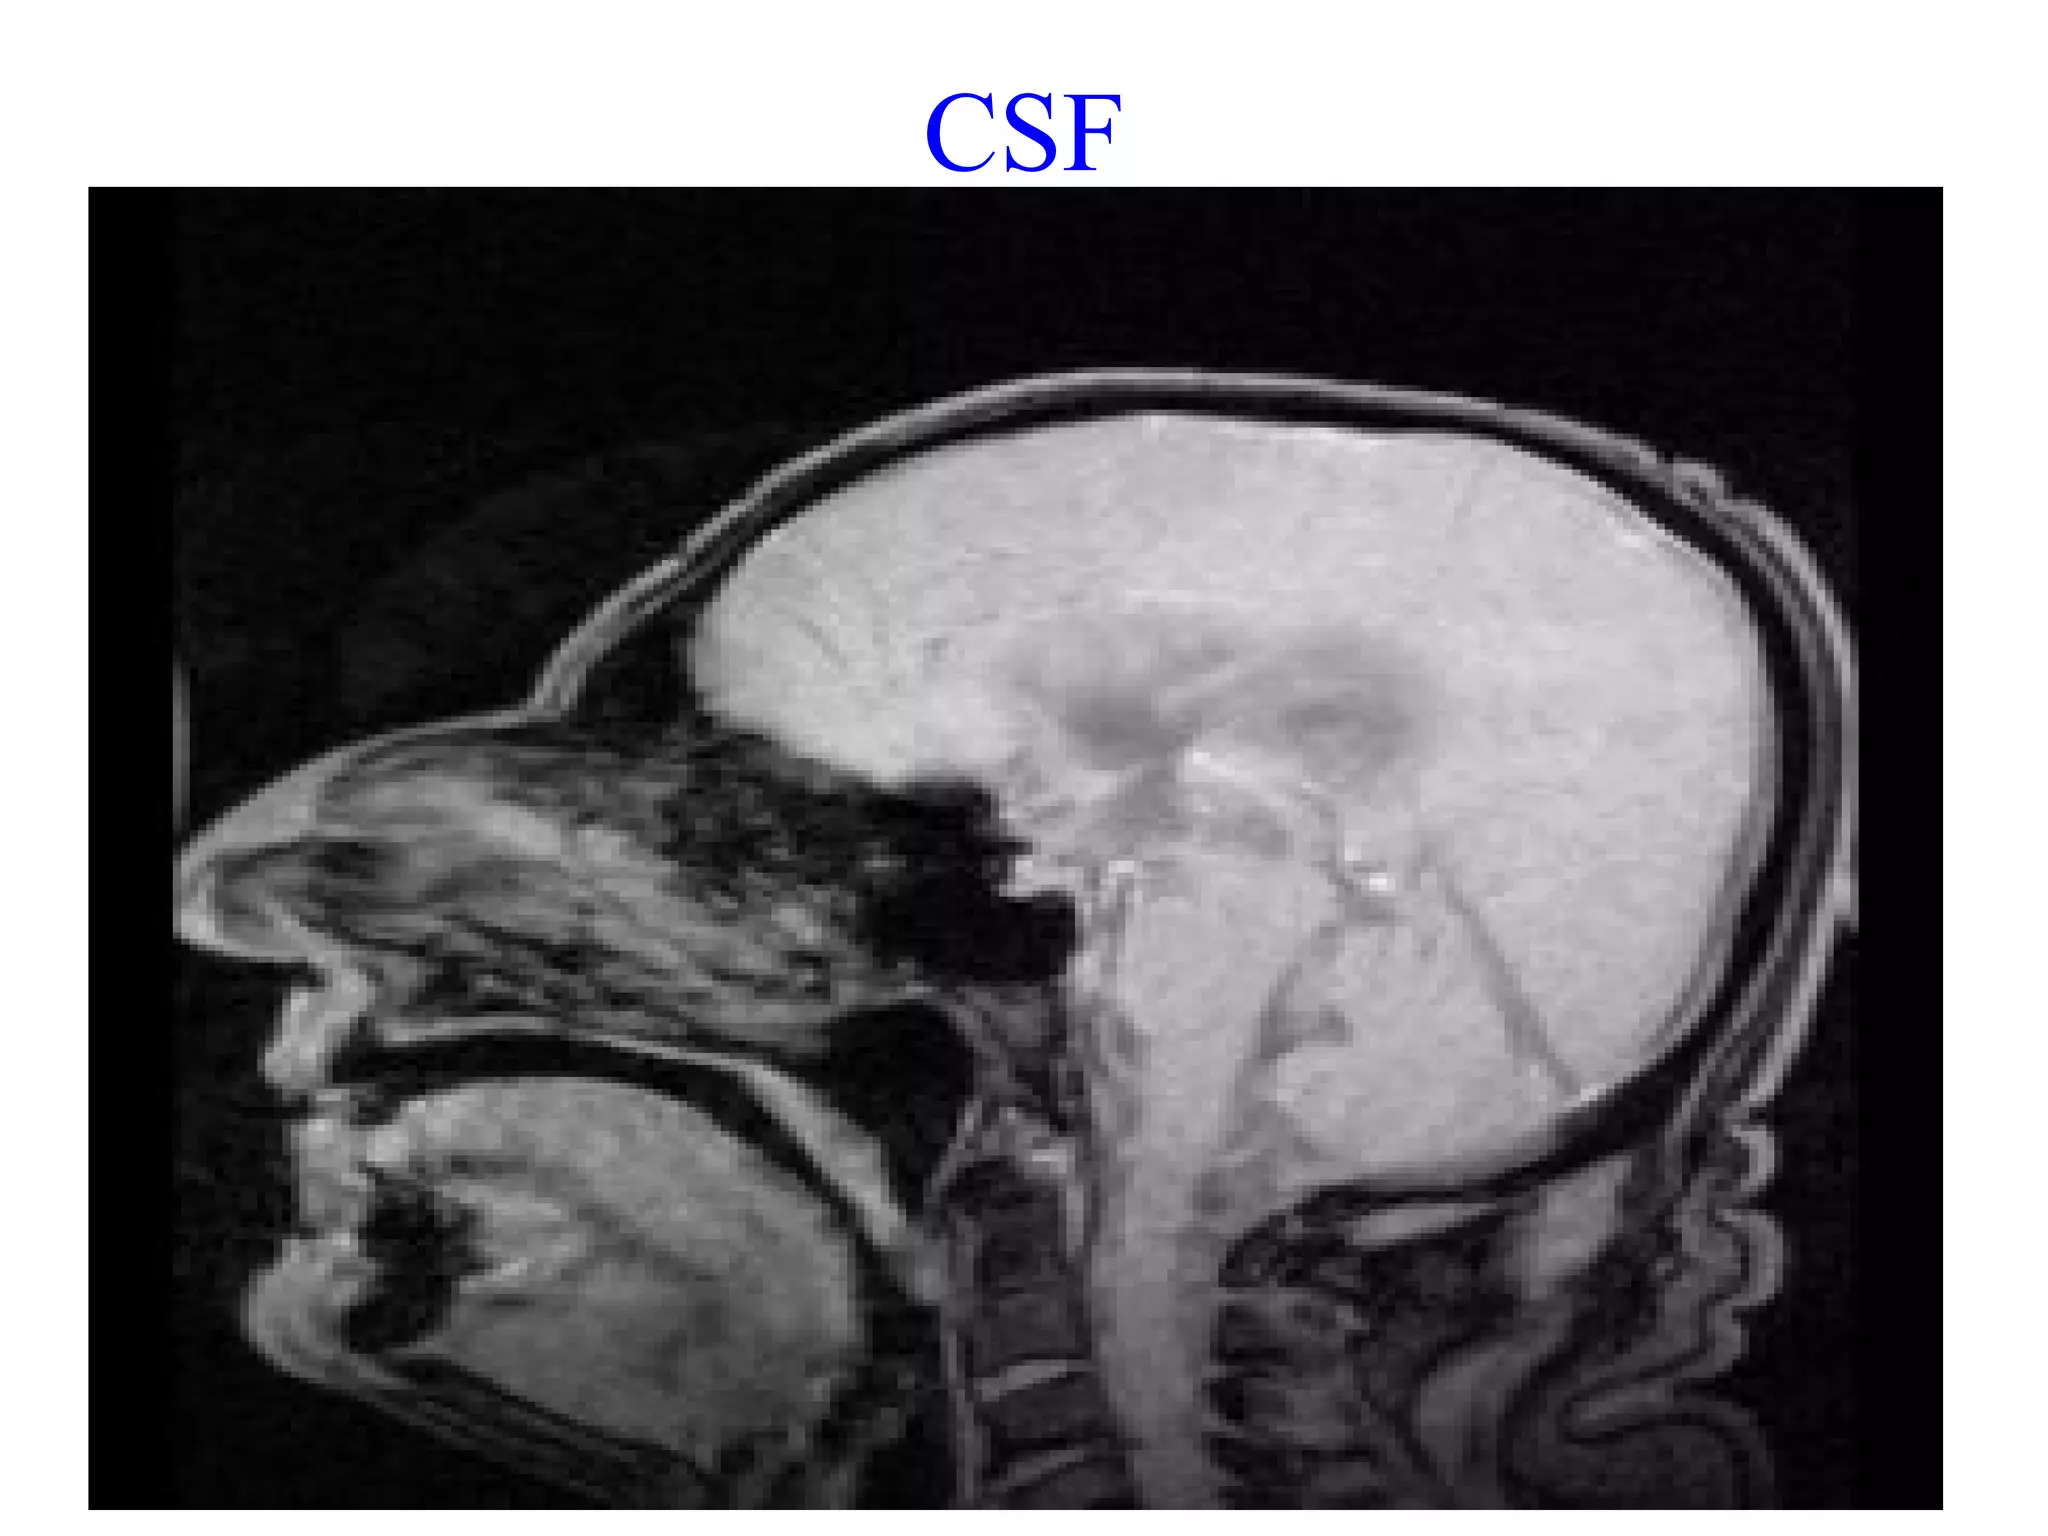

 Both the brain and spinal cord are covered by three

protective membranes referred to as the meninges

 Between the arachnoid layer and the pia mater is a

space called the subarachnoid space. It contains a clear,

colorless fluid referred to as Cerebrospinal Fluid (CSF).

 Supply nutrients to the nervous tissue,remove metabolic

wastes and produce a mechanical barrier